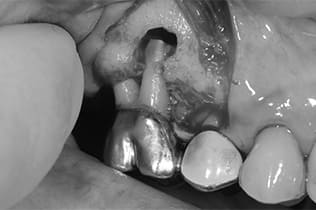

Case08

-

- 原因

- 歯根嚢胞、重度カリエス

- 治療内容

- 再植手術、クラウンレングスニング

- 治療費用

- ¥99,000

他院で根管治療を行ったが、なかなか治らず、抜歯を宣告されたとのことでご来院された患者様です。歯がかなり削られており、また、歯根の根尖部の病変が大きく、嚢胞化しているため、クラウンレングスニングと再植歯根端手術を同時に行いました。違和感もなくなり、大変満足されています。

<リスク・副作用>

外科手術のため、術後に出血、痛みや腫れ、違和感を伴います。口腔内の状態によっては適応できないことがあります。歯根端切除で治らなければ抜歯を検討しなくていけない場合もあります。